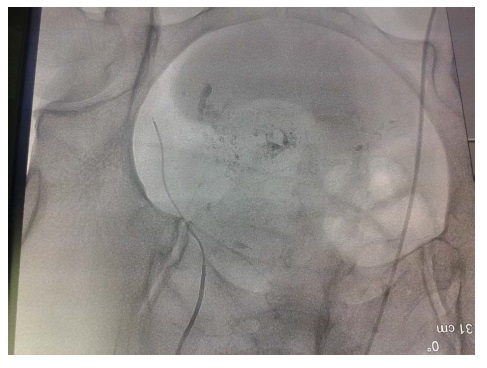

There are still some doubts regarding the intra-arterial dose that is recommended for treating ectopic masses in cesarean scars (Figure 1). In our case uterine artery embolization with methotrexate infusion combined curettage may be the preferred mode of treatment (Figure 2). But it failed in our case. Nowadays we have to rely on ‘good practice points’ based on anecdotal case reports and small case series. More research is required in this subject (Figure 3, 3A, 3B and 3C). So that setting up multicenter collaboration would encourage robust evidence-based studies essential for making recommendations for practice (Figure 4).

Figure 3: Bilateral uterine angiography before and after uterine artery embolization

Figure 3A: Uterine arteries were enlarged by means of hypervascular infusion of methotrexate before uterine artery embolization.

Figure 3B: Unilateral occlusion was successfully performed.

Figure 3C: Bilateral arterial occlusion was confirmed after the uterine artery embolization and no extravasation was observed.